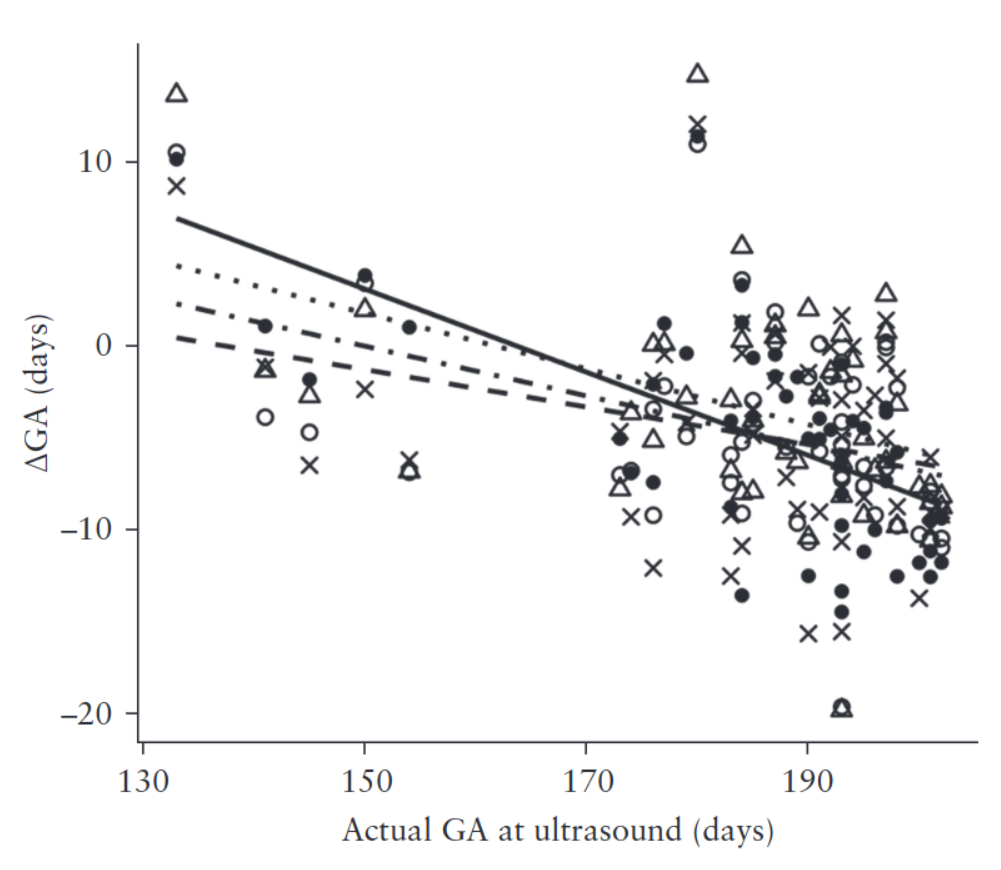

Learning-based prediction of gestational age from ultrasound images of the fetal brain

Medical Image Analysis

·

01 Apr 2015

·

doi:10.1016/j.media.2014.12.006